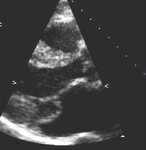

Corte apical de 4 câmaras de folheto mitral posterior instável

Do acervo de Samir Kapadia e Mehdi H. Shishehbor